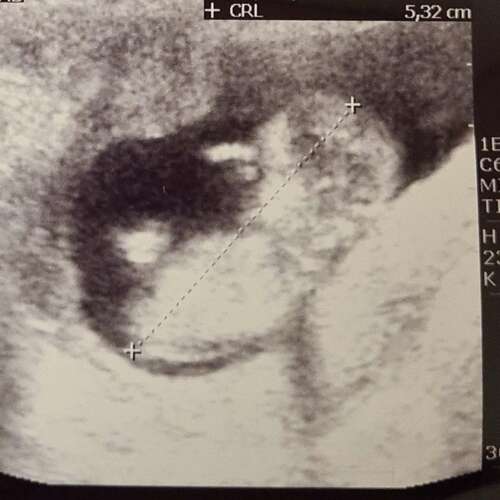

Foto 2: ook 13+1 week. Zelf denk ik het niet te kunnen zien

Ik waag toch een gokje: Meisje